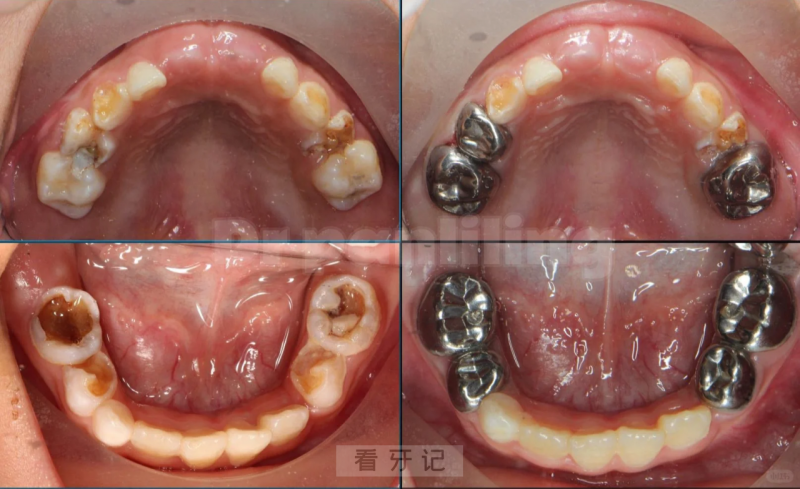

③牙体严重缺损:当牙齿因龋坏(蛀牙)、外伤(如磕碰)、磨损,牙冠可以包裹并保护剩余的牙体组织,恢复牙齿的形状和功能。